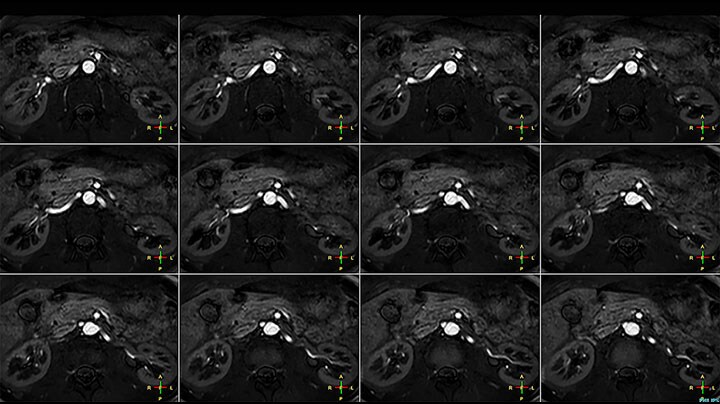

Bildgebung der Nierenarterien ohne Kontrastmittel mit Prodiva 1.5T.